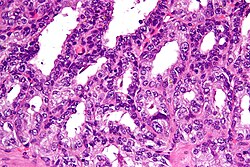

Prostate carcinoma

Prostate carcinoma. H&E stain.

LM major criteria: abnormal architecture (increased gland density, usu. small circular glands, "infiltrative growth" pattern), basal cells lost, cytological abnormalities (nuclear enlargement, nucleoli); minor criteria: nuclear hyperchromasia, wispy blue mucin, pink amorphous secretions, intraluminal crystalloid, amphophilic cytoplasm, adjacent HGPIN, mitoses

LM DDx high-grade prostatic intraepithelial neoplasia, atypical small acinar proliferation (biopsy only), prostatic atrophy, seminal vesicle, basal cell hyperplasia, others